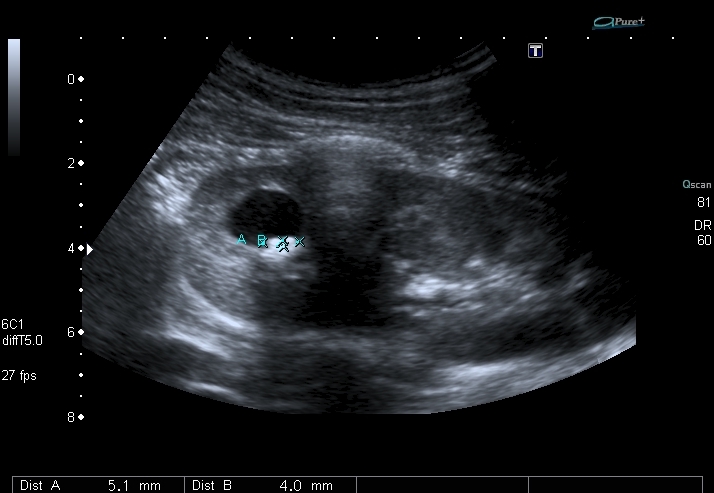

Скан области интереса

Мальчика выписали без рентгенологического исследования. Будем обходиться УЗИ. Почему это не может быть кистой с конкрементами? Формирование конкрементов в кисте менее вероятно, чем в дивертикуле чашечки или в расширенной чашечке при синроме Фрейли. Но полость уж больно круглая, да и связи с ЧЛС и конфликта с интраренальным сосудом сколько не смотрел, я не увидел.

Полость в врехнем полюсе, но на Фрейли не похоже - нет сосуда на ЦДК под полостью. Была мысль о дивертикуле чашечки, будем дообследовать путём экскреторной урогфии, изображения выложу.KapustinSV писал(а):Cлева "голова" или справа?